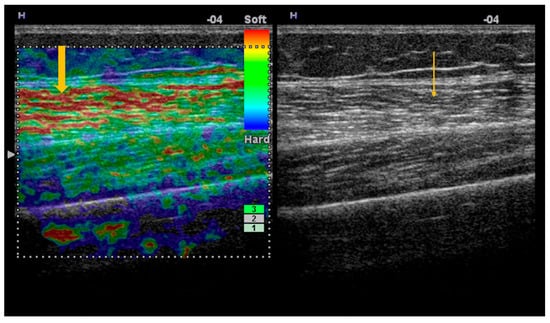

The Role of Imaging Techniques in the Evaluation of Extraglandular Manifestations in Patients with Sjögren’s Syndrome

Sjögren’s syndrome is a chronic autoimmune disease marked by lymphocytic infiltration of the exocrine glands and the development of sicca symptoms, yet some patients also develop extraglandular involvement. Imaging has become relevant for describing these systemic features and supporting clinical assessment. This review discusses the roles of ultrasonography, elastography, computed tomography, and magnetic resonance imaging in evaluating multisystem disease associated with Sjögren’s syndrome. Ultrasonography and elastography help assess muscular involvement by showing changes in echogenicity and stiffness that reflect inflammation and later tissue remodeling. In joints, ultrasound can detect synovitis, tenosynovitis, and early erosive changes, including abnormalities not yet evident on examination. Pulmonary disease, most often with interstitial lung involvement, is best evaluated with high-resolution computed tomography, which remains the most reliable imaging modality for distinguishing interstitial patterns. Magnetic resonance imaging is valuable in assessing neurological complications. It can reveal ischemic and demyelinating lesions, neuromyelitis optica spectrum features, or pseudotumoral appearances. Imaging is also essential for detecting lymphoproliferative complications, for which ultrasound and magnetic resonance imaging can reveal characteristic structural and diffusion-weighted imaging findings. When combined with clinical and laboratory information, these imaging methods improve early recognition of systemic involvement and support accurate monitoring of disease progression in Sjögren’s syndrome. Full article